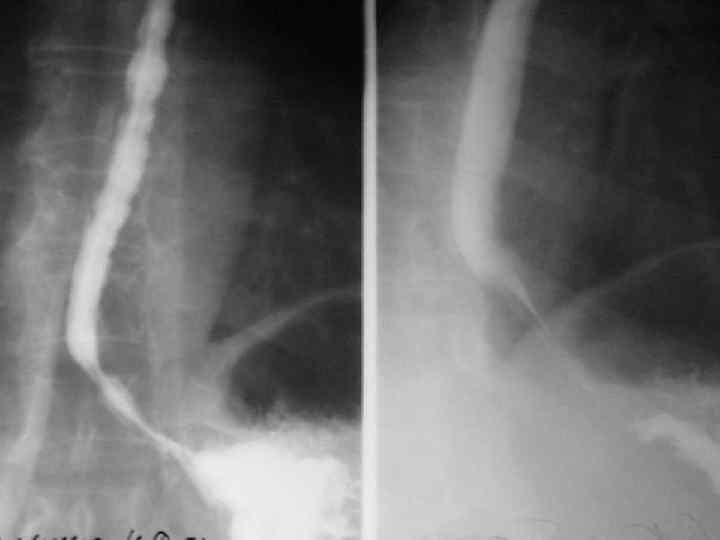

Дифференциальная диагностика Кардиоспазм Ахалазия кардии Внезапное начало заболевания Постепенное прогрессирование заболевания Парадоксальная дисфагия Не характерно Интенсивная загрудинная боль Не характерно Регургитация вскоре после Регургитация через еды несколько часов после еды Моторика пищевода усилена Моторика пищевода угнетена

Кардиоспазм Ахалазия кардии Терминальный отдел в виде конуса редиски Опорожнение пишевода в Начало эвакуации зависит виде выжимания контраста от высоты столба контраста через узкий сегмент Незначительное Значительное расширении узкого сегмента при прохождении контраста Градиент пищеводножелудочного давления более 20 мм рт. ст. Градиент пищеводножелудочного давления менее 20 мм рт. ст.